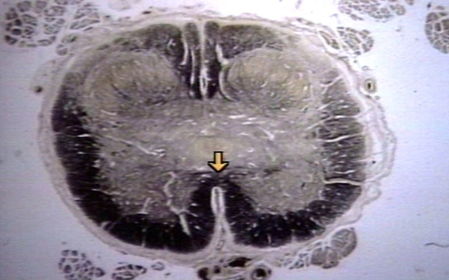

Anterior Horn (ventral) Innervates skeletal muscles

Lateral HOrn Innervate cardiac muscles.

Posterior Horn (Dorsal) Receives sensory info. like touch.

Gray Commissure communication route between R&L sides of gray matter.

White commissure Connects the white matter to the R&L sides of spinal cord.

Anterior Funiculus Lateral Funiculus posterior Funiculus Transmit nerve impulses vertically along spinal cord.

Anterior median fissure Divides spinal cord into 2 anterior sections

Posterior median sulcus median portion of the spinal nerves enter the spinal cord.

central canal houses the spinal cord and CSF fluid